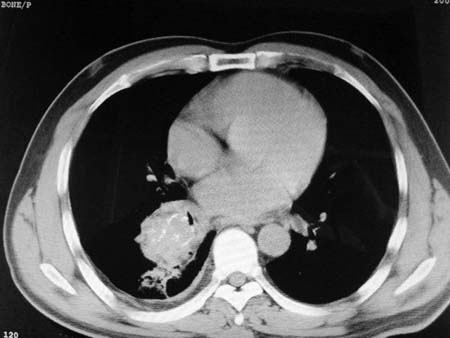

以下是引用qian在2008-4-27 17:02:00的发言:[br]考虑右下肺肺段隔离症伴有感染,建议做增强看看。

以下是引用zsl6918在2008-4-27 17:13:00的发言:[br]考虑右肺下叶炎性病变可能性大,建议抗炎治疗后复查,现有资料不能完全除外肺癌可能。